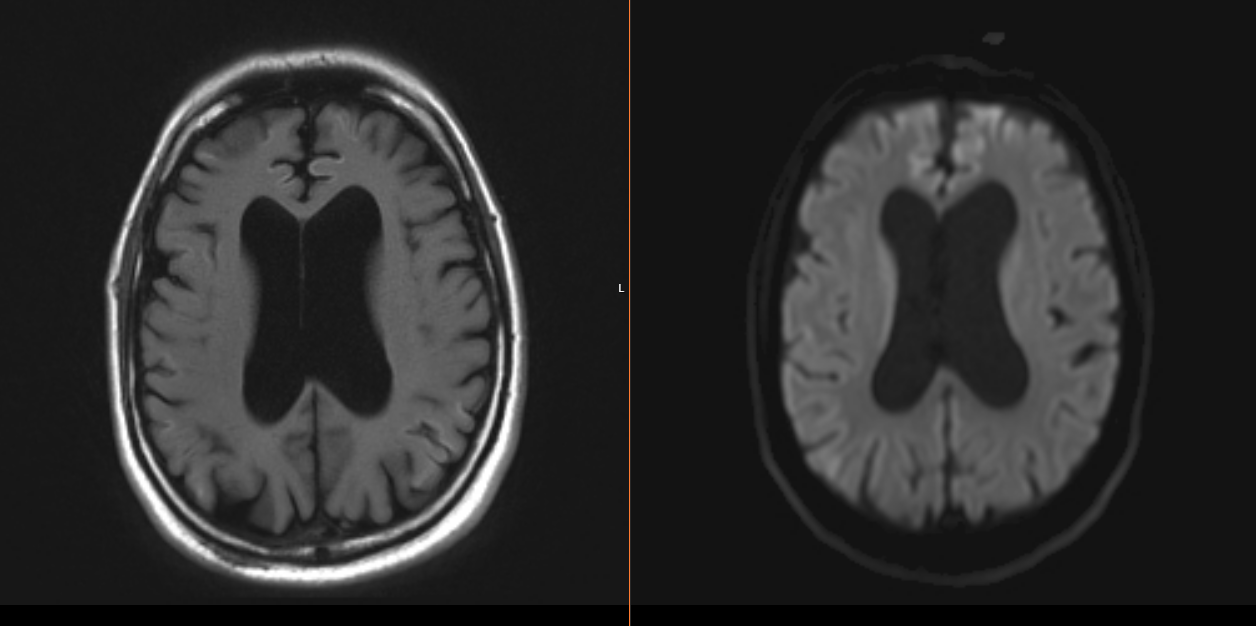

Case Presentation: A 48 y/o man with history of chronic methamphetamine use, schizophrenia, and bipolar disorder presented after being found unconscious associated with urinary incontinence. He was treated for toxic metabolic encephalopathy in setting of sepsis from urinary tract infection and multifocal pneumonia. However, his mental status declined despite initiation of antibiotics. He was alert and oriented to name only. At baseline, he is fully alert and oriented. He was able to follow simple commands with notable expressive aphasia, impaired short-term memory, Argyll Robertson pupils and hyperreflexia. Further questioning from family revealed a one-year rapid decline in his memory and behavior with increasing delusions and visual hallucinations, that acutely progressed two weeks prior to presentation. Given his cognitive decline, he completed a course of methylprednisolone for possible autoimmune encephalopathy without improvement. Infectious workup revealed RPR titer of 1:64 and positive serum treponema pallidum antibody. MRI brain showed diffuse frontal, parietal, and temporal lobe cortical hyperintensity and caudate diffusion. CTA chest displayed large right loculated empyema with chest tube placed for drainage. He underwent a lumbar puncture with negative cerebrospinal fluid (CSF) BioFire but positive CSF treponema pallidum antibody. Repeat RPR titer was 1:128. He started treatment for neurosyphilis with IV Penicillin G. Despite treatment, his mental status did not improve. Electroencephalogram was unremarkable. 14-3-3 CSF titer was elevated (>138,000 AU/mL), with elevated tau protein (>20,000) and indeterminate RT-QUIC. Despite the indeterminate RT-QUIC, neuroimaging findings and extremely elevated 14-3-3 made a diagnosis of Creutzfeldt-Jacob disease (CJD) with neurology evaluation. His empyema was controlled with thoracotomy and decortication.

Discussion: Neurosyphilis can be subdivided into early disease, with findings of asymptomatic neurosyphilis, meningitis, ocular-or oto-syphilis, or late disease with findings of general paresis or tabes dorsalis. The diagnostic criteria for CJD includes progressive dementia, startle myoclonus, visual disturbances, ataxia and akinetic mutism. 14-3-3 are non-specific markers of neuronal injury and have been reported to be elevated in few cases of neurosyphilis, however, the RT-QUIC is a highly sensitive and specific marker for CJD. In our patient’s case, it was indeterminate, but the cortical ribboning on MRI brain coupled with the progressive cognitive decline, visual disturbances and personality changes pointed towards CJD. Typical MRI findings include hyperintense signal on diffuse weighted imaging, fluid-attenuated inversion recovery T2-weighted images involving the cerebral cortex and corpus striatum. Neurosyphilis is known to imitate other pathologies as the “great mimicker” in medicine. However, our case highlights the importance of pursuing a complete workup, with a multidisciplinary team. This led to a diagnosis of CJD, with neurosyphilis as a confounding factor.